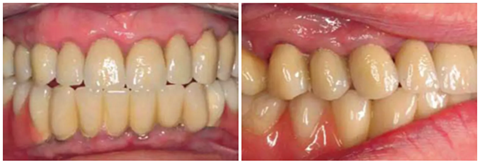

圖17& 18:Katharina Dietz-Epple醫(yī)生(Aalen, Germany)完成的冠修復(fù)(上頜)及可摘局部義齒修復(fù)(下頜)。

有一位病人因為口腔鱗狀細(xì)胞癌而進(jìn)行了部分舌和口底的切除術(shù),并進(jìn)行了輔助放療。盡管由于組織的纖維化,外科準(zhǔn)備及創(chuàng)口縫合時變的非常困難,但患者的種植手術(shù)最終仍然成功了?;颊吲宕髁肆甑牧x齒,并且一直沒有出現(xiàn)問題。這部分的臨床過程及義齒情況詳見于圖8-18.